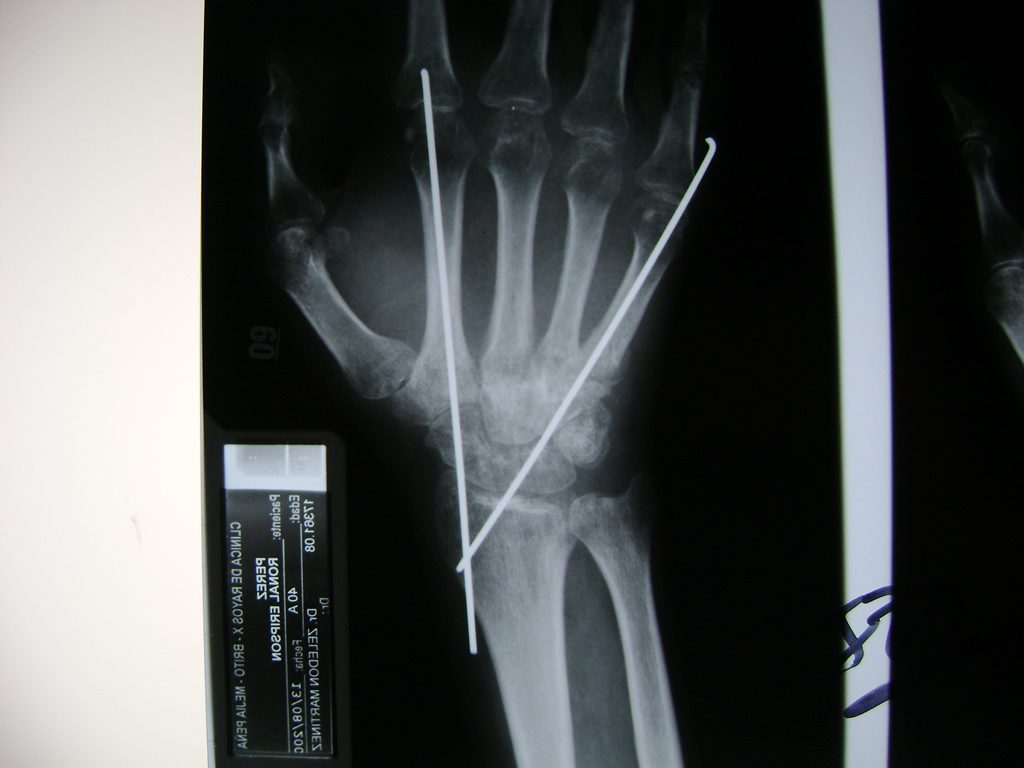

Cirugía de Muñeca y Mano

Los procedimientos más comunes en cirugía de la mano son aquellos destinados a reparar traumatismos, incluyendo lesiones de tendones, nervios, vasos sanguíneos, y articulaciones; huesos fracturados; y quemaduras, cortes, y otros daños de la piel.